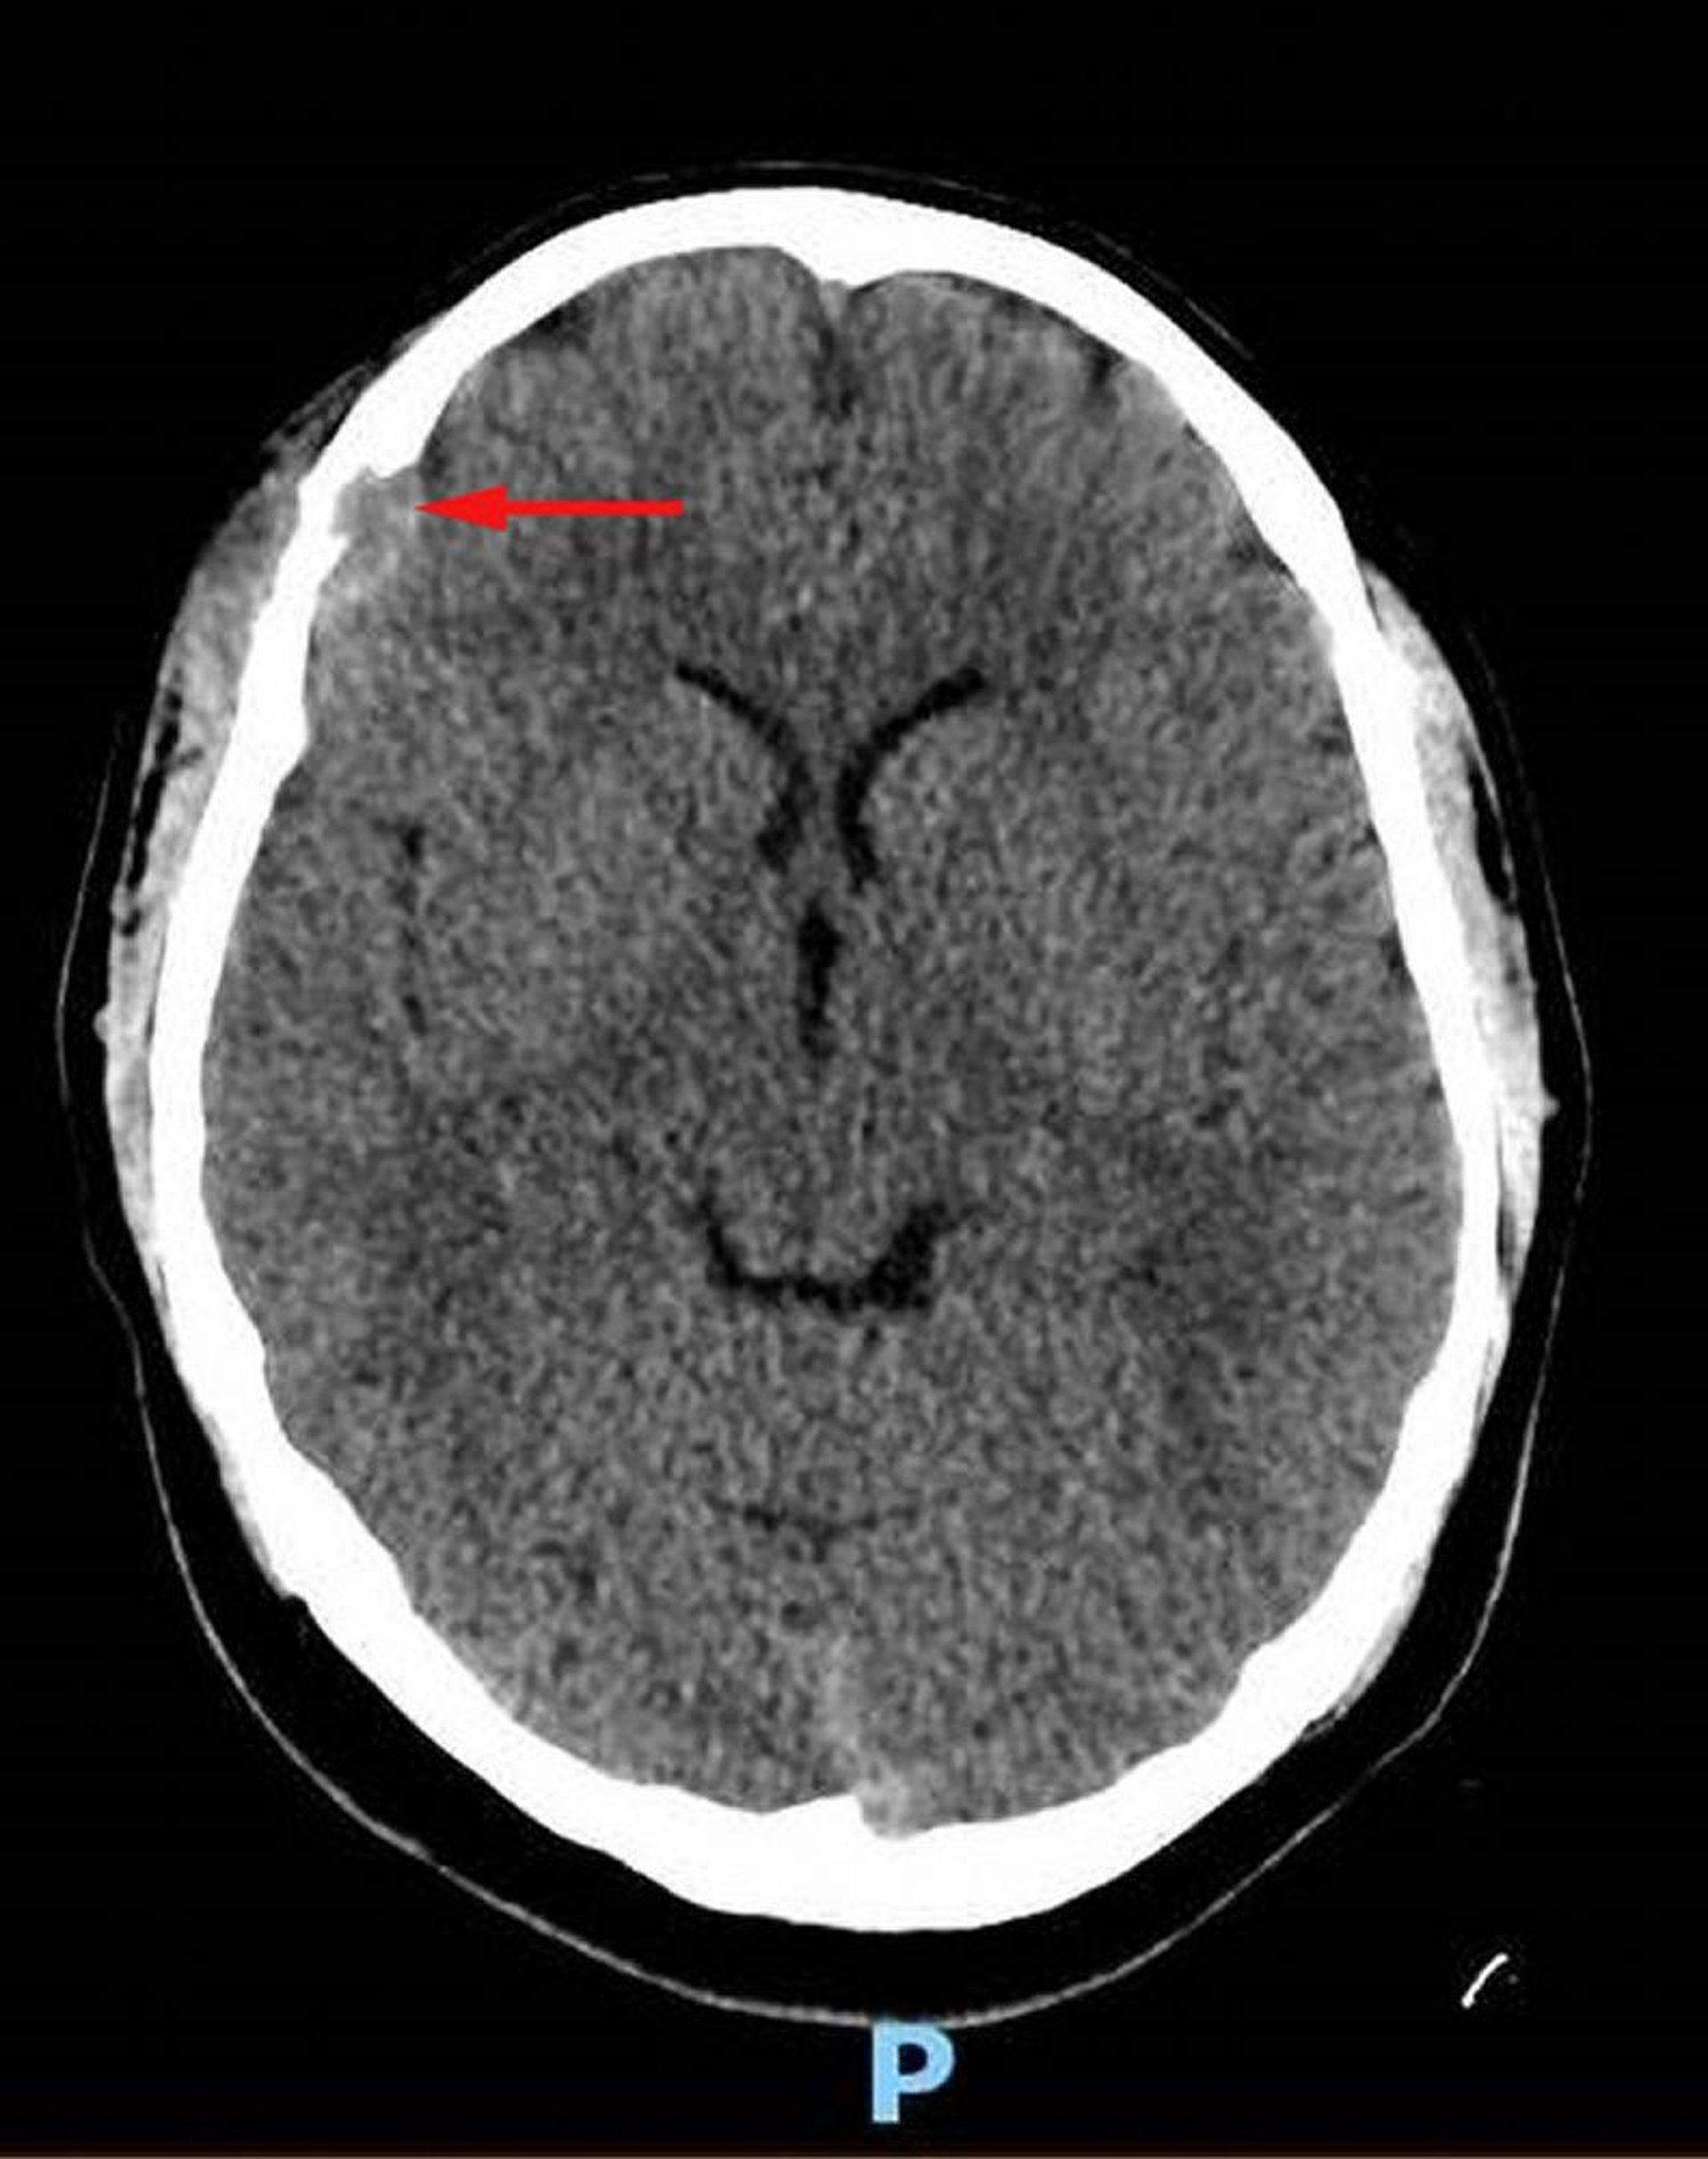

Langerhans-Zell-Histiozytose (Kopf-CT)

Diese Abbildung zeigt eine Weichgewebeläsion im rechten Stirnbein mit begleitender knöcherner Zerstörung und intrakranieller Ausdehnung des Weichgewebes in den Duralraum (roter Pfeil). Asymmetrisches, über der Kopfhaut liegendes Weichteilgewebe ist vorhanden. Die Biopsie war diagnostisch für Langerhans-Zell-Histiozytose.

Image courtesy of Carolyn Fein Levy, MD, and Jeffrey M. Lipton, MD, PhD.